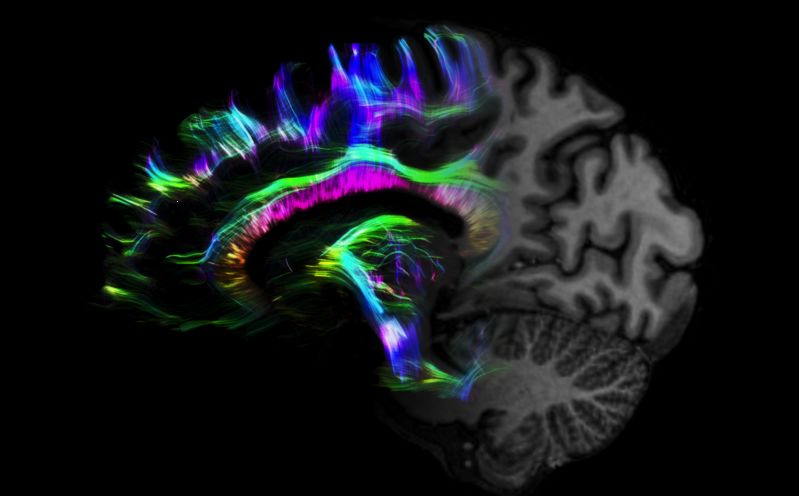

1毫米的各向同性分辨率DTI:神經(jīng)纖維束的交叉細節(jié)顯示